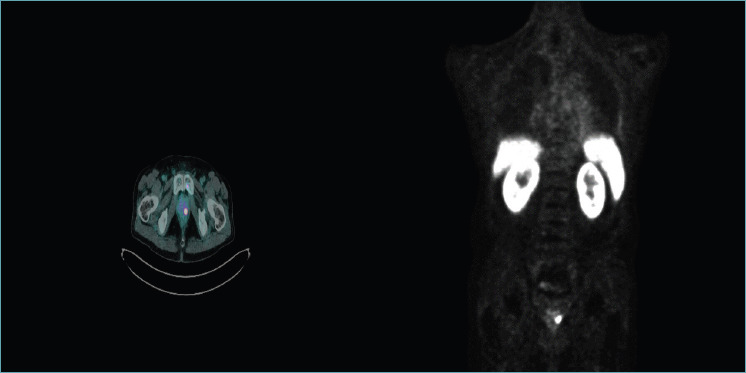

Multiparametric magnetic resonance imaging (mpMRI) has improved systematic prostate biopsy procedures in the diagnosis of clinically significant prostate cancer (csPCa) by reducing the number of unnecessary biopsies; numerous level one evidence studies have confirmed the accuracy of MRI-targeted biopsy, but, still today, systematic prostate biopsy is recommended to reduce the 15-20% false negative rate of mpMRI. New advanced imaging has been proposed to detect suspicious lesions and perform targeted biopsies especially when mpMRI cannot be performed. Transrectal ultrasound (TRUS) modalities are emerging as methods with greater sensitivity and specificity for the detection of PCa compared to the traditional TRUS; these techniques include elastography and contrast-enhanced ultrasound, as well as improved B-mode and Doppler techniques. These modalities can be combined to define a novel ultrasound approach: multiparametric ultrasound (mpUS). More recently, micro-ultrasound (MicroUS) and prostate-specific membrane antigen (PSMA) positron emission tomography/computed tomography (PET/CT) have demonstrated to be sensitive for the detection of primary prostatic lesions resulting highly correlated with the aggressiveness of the primary prostatic tumor. In parallel, artificial intelligence is advancing and is set out to deeply change both radiology and pathology. In this study we address the role, advantages and shortcomings of novel imaging techniques for Pca, and discuss future directions including the applications of artificial intelligence-based techniques to imaging as well as histology. The significance of these findings for the practicing pathologist is discussed.

Abstract Image